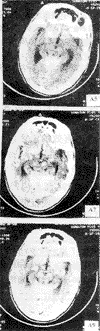

人脑CT(示四叠体)

四叠体(corpora quadrigemina)